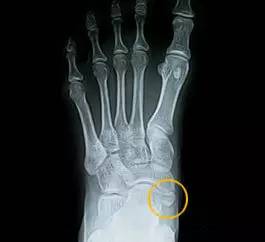

当发生足副舟骨疼痛时,首先要拍X光确诊,并确定分型。

足副舟骨是人体最大的副骨,可分为3型。

一型不与舟骨相连,一般无症状。

二型副舟骨是舟骨的一部分,由结节部纤维软骨板分开。进一步分为2A和2B型。

三型二者有骨桥连接,形成角状舟骨。